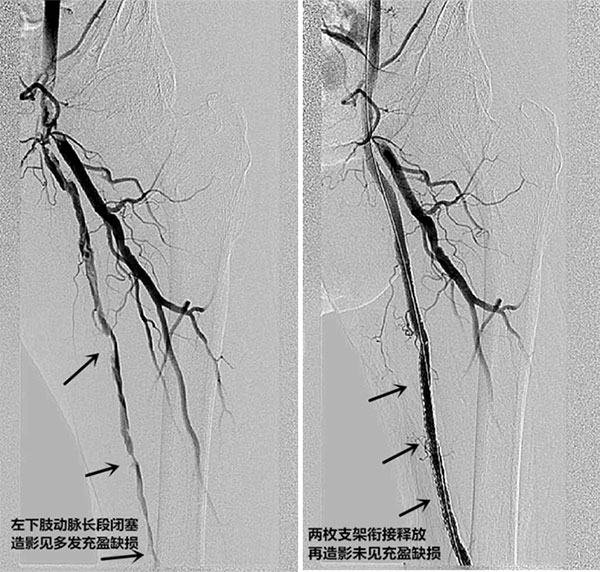

在短时间的术前检查和准备后,刘婆婆被送入介入室,陆骊工主任亲自主刀行腔内介入手术。术中引入血管鞘后送导管于高位造影,左下肢动脉见多处充盈缺损,提示下肢血管多发性粥样硬化斑块形成,其中股浅-股深动脉分叉处见血栓形成,考虑左侧股动脉血栓堵塞及血管硬化性闭塞,遂引入翻山鞘后于左侧股动脉-腘动脉放置血管支架2枚,再造影见下肢血流通畅情况较前明显好转。

整个手术历时近2个小时,比普通的血管狭窄腔内成形术耗时多了差不多一倍。术后据陆主任分析,术中难点主要在于患者血管多发粥样斑块形成,且股-腘动脉闭塞段达15cm,而且动脉变形扭曲、病变段钙化严重,这会导致导管和导丝难以通过闭塞段,若术中操作不慎出现血栓脱落,会引起严重并发症。手术能否成功关键在于导丝能否穿过病变进入远端真腔(?)。血管腔内介入手术疗效明显,仅是术后当晚,刘婆婆下肢疼痛缓解,第二天足部皮温回复温暖、足背动脉搏动恢复。经过后续抗凝及对症支持治疗,术后第三天可站立行走并出院。